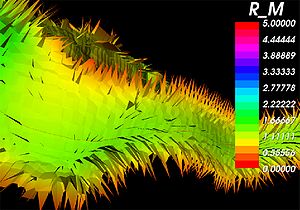

Publication: PLoS One. 2015 Oct 7;10(10):e0139434. PMID: 26444010 | PDF Authors: Tax CM, Chamberland M, van Stralen M, Viergever MA, Whittingstall K, Fortin D, Descoteaux M, Leemans A. Institution: Image Sciences Institute, University Medical Center Utrecht, Utrecht, The Netherlands. Background/Purpose: Fiber tractography plays an important role in exploring the architectural organization of fiber trajectories, both in fundamental neuroscience and in clinical applications. With the advent of diffusion MRI (dMRI) approaches that can also model "crossing fibers", the complexity of the fiber network as reconstructed with tractography has increased tremendously. Many pathways interdigitate and overlap, which hampers an unequivocal 3D visualization of the network and impedes an efficient study of its organization. We propose a novel fiber tractography visualization approach that interactively and selectively adapts the transparency rendering of fiber trajectories as a function of their orientation to enhance the visibility of the spatial context. More specifically, pathways that are oriented (locally or globally) along a user-specified opacity axis can be made more transparent or opaque. This substantially improves the 3D visualization of the fiber network and the exploration of tissue configurations that would otherwise be largely covered by other pathways. We present examples of fiber bundle extraction and neurosurgical planning cases where the added benefit of our new visualization scheme is demonstrated over conventional fiber visualization approaches. Funding:

|